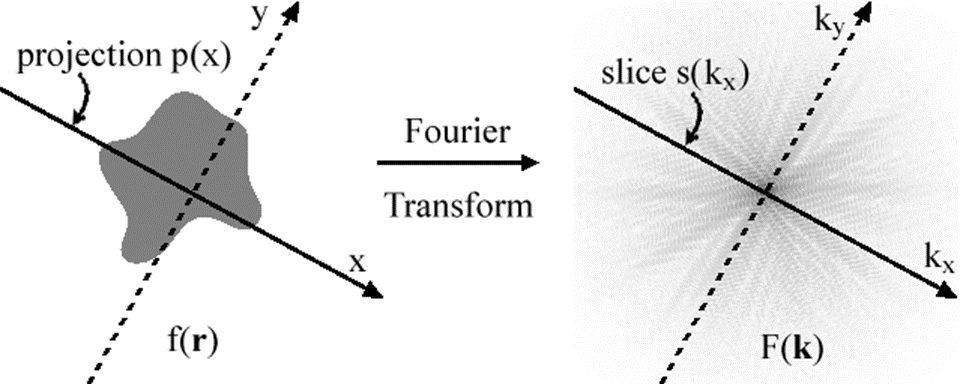

Image reconstruct works because of the “Fourier projection theorem” or Projection-slice theorem” [13]. This theorem states that the integral of a shape projection along some axis is a slice of the 2d Fourier transform of that shape projected along the same axis. A graphical view of this theorem can be seen in Figure 1. This method is called back projection. Plotting all these back projected angles creates a sinogram and example of which can be seen in Figure 2. This figure shows sinogram of a basic test image that can be found in Appendix B: basic image This theorem also states that an infinite number of projects are taken at different angles and the image can be perfectly reconstructed.

Figure 1: example of Fourier projection theorem source: Public Domain, https://commons.wikimedia.org/w/index.php?curid=646788

Figure 1: example of Fourier projection theorem source: Public Domain, https://commons.wikimedia.org/w/index.php?curid=646788